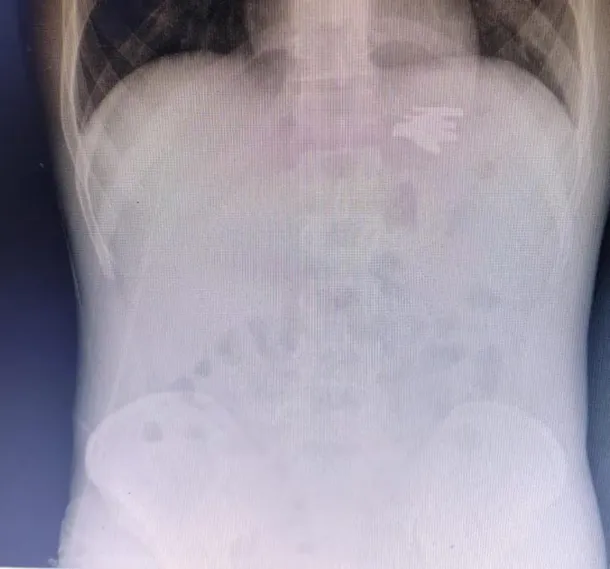

El interno, identificado como A.C., de 27 años, fue ingresado de urgencia al centro de salud con una lesión interna provocada por la ingesta de un tenedor. Ante esta situación, los médicos indicaron que debía permanecer internado para que pudieran evaluar su condición clínica y definir los pasos del tratamiento médico.